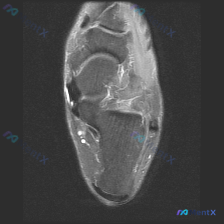

看到这个踝关节MRI的病例,整理了完整的影像资料和分析思路,和大家分享讨论。 病例影像基础信息 这是踝关节MRI T2加权轴位图像,扫描层面为踝关节远端,可见距骨体及周围软组织结构,图像对比度满足观察要求,T2加权像液体呈高信号。 核心影像发现 1. 骨结构:距骨及周围骨性结构骨髓无异常高信号,骨皮...